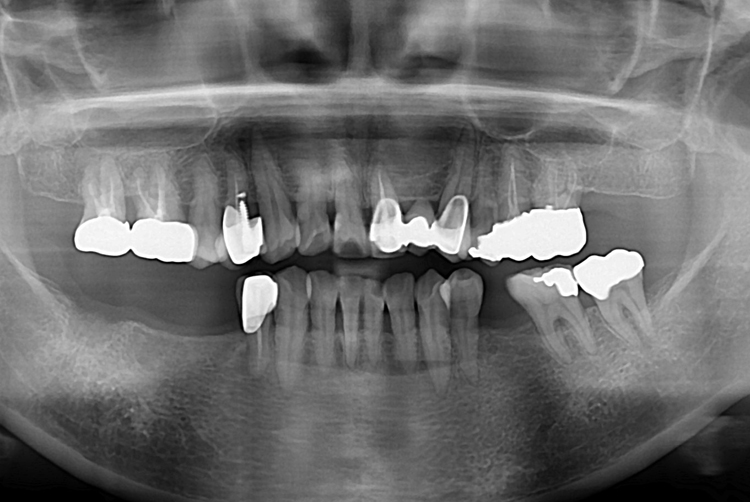

[임플란트] 어금니 임플란트

치료후 : 2017-08-09

세종치과는 많은 환자와 다양한 케이스를 바탕으로

항상 편안한 임플란트 수술을 제공하고자 노력하고,

오래동안 튼튼히 쓸 수 있는 임플란트 수술을 가장 큰 목표로 삼고 있습니다.